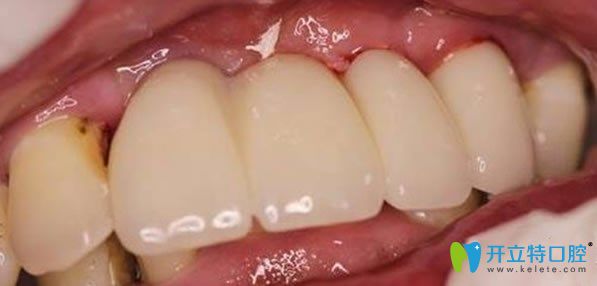

無(wú)錫佳士潔口腔多顆牙缺失微創(chuàng)無(wú)痛種植牙術(shù)后效果圖:

種植牙手術(shù)后需要5個(gè)月的恢復(fù)期,種植體和牙槽骨緊密結(jié)合后,裝上牙冠,即刻承重??吹竭@整齊的牙齒,劉媽心里美滋滋的。無(wú)錫佳士潔口腔李永平院長(zhǎng),德國(guó)種植牙技術(shù)增強(qiáng)了牙齒的咀嚼功能,吃嘛嘛香,劉媽一直夸贊種植牙是兒子送給她的禮物。